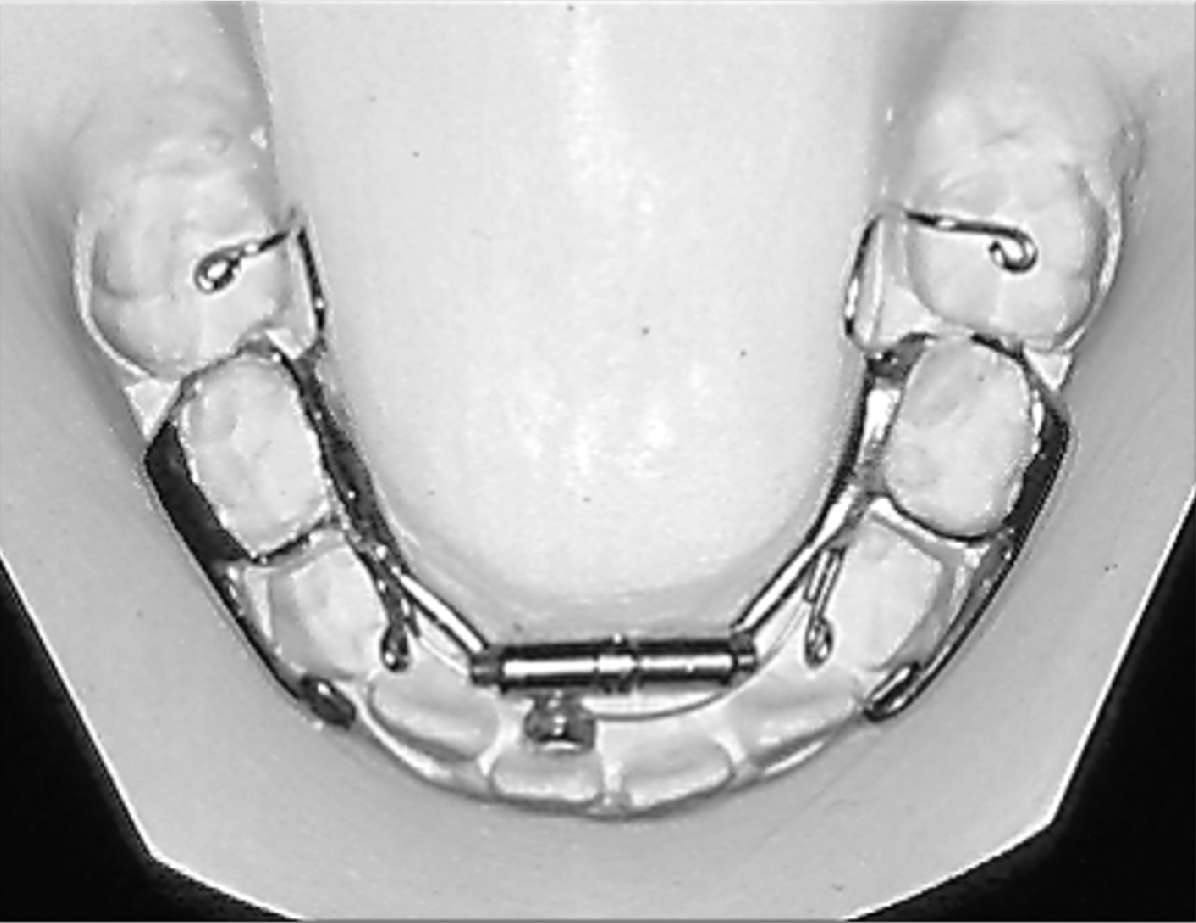

The Williams appliance is banded on the deciduous second molars in the “early” mixed dentition, and on the permanent first molars in the “late” mixed dentition. It consists of a special midline expansion screw, attachments contacting the lingual surface of all of the posterior teeth, and a nickel titanium arch wire that can be activated against the lower incisors. Separators are places on the patient while the appliance is being fabricated using the indirect banding technique.

A very common modification of the Williams appliance is to use buccal tubes on the molar bands when the appliance is placed on the permanent first molars. Delta Force brackets can be placed on all of the permanent teeth that have erupted anterior to the permanent first molars. A .020 x .020 thermal activated, multi-gradient force, nickel titanium arch wire is used in conjunction with the Williams appliance to level, align, and torque the teeth as the arch is being developed.